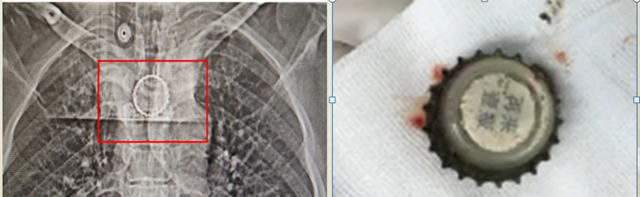

颈胸部CT显示了异物的形态、位置及与周围组织的关系

成年人夜宵豪饮不慎把啤酒盖误吞食管